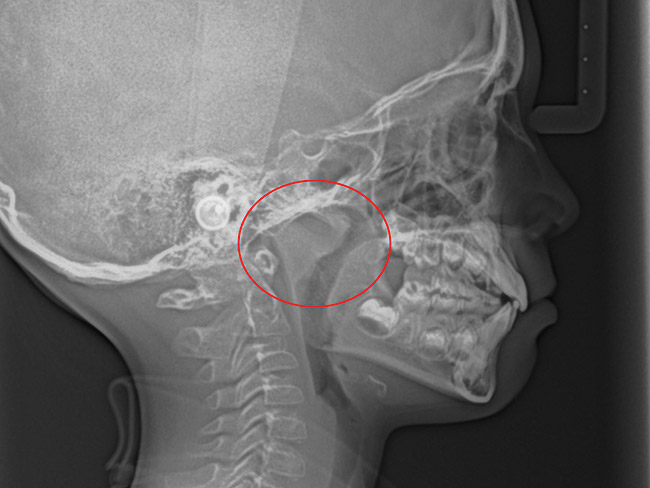

(15.) Cephalometric evaluation demonstrates significant tonsillar blockage of the airway and bimaxillary retursion.

Figure 15

(21.) Six-year-old male presents nocturnal bruxism, habitual snoring, and behavioral issues. PSG reports an AHI of 9.6/hr and respiratory effort–related arousal (RERA) of 14.2/hr (Case provided by Kathy French, DDS).

Figure 21

(22.) Radiograph highlights the obstructed nasal airway preoperatively. Three months after T&A, another PSG demonstrated an AHI of 0.3 and RERA of 0.0/hr.

Figure 22